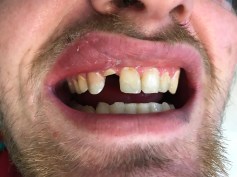

Emergency Visit #6 MIFL, #8 MIDFL, #9 MIFL

*Extraction & bone graft planned for #7 future implant